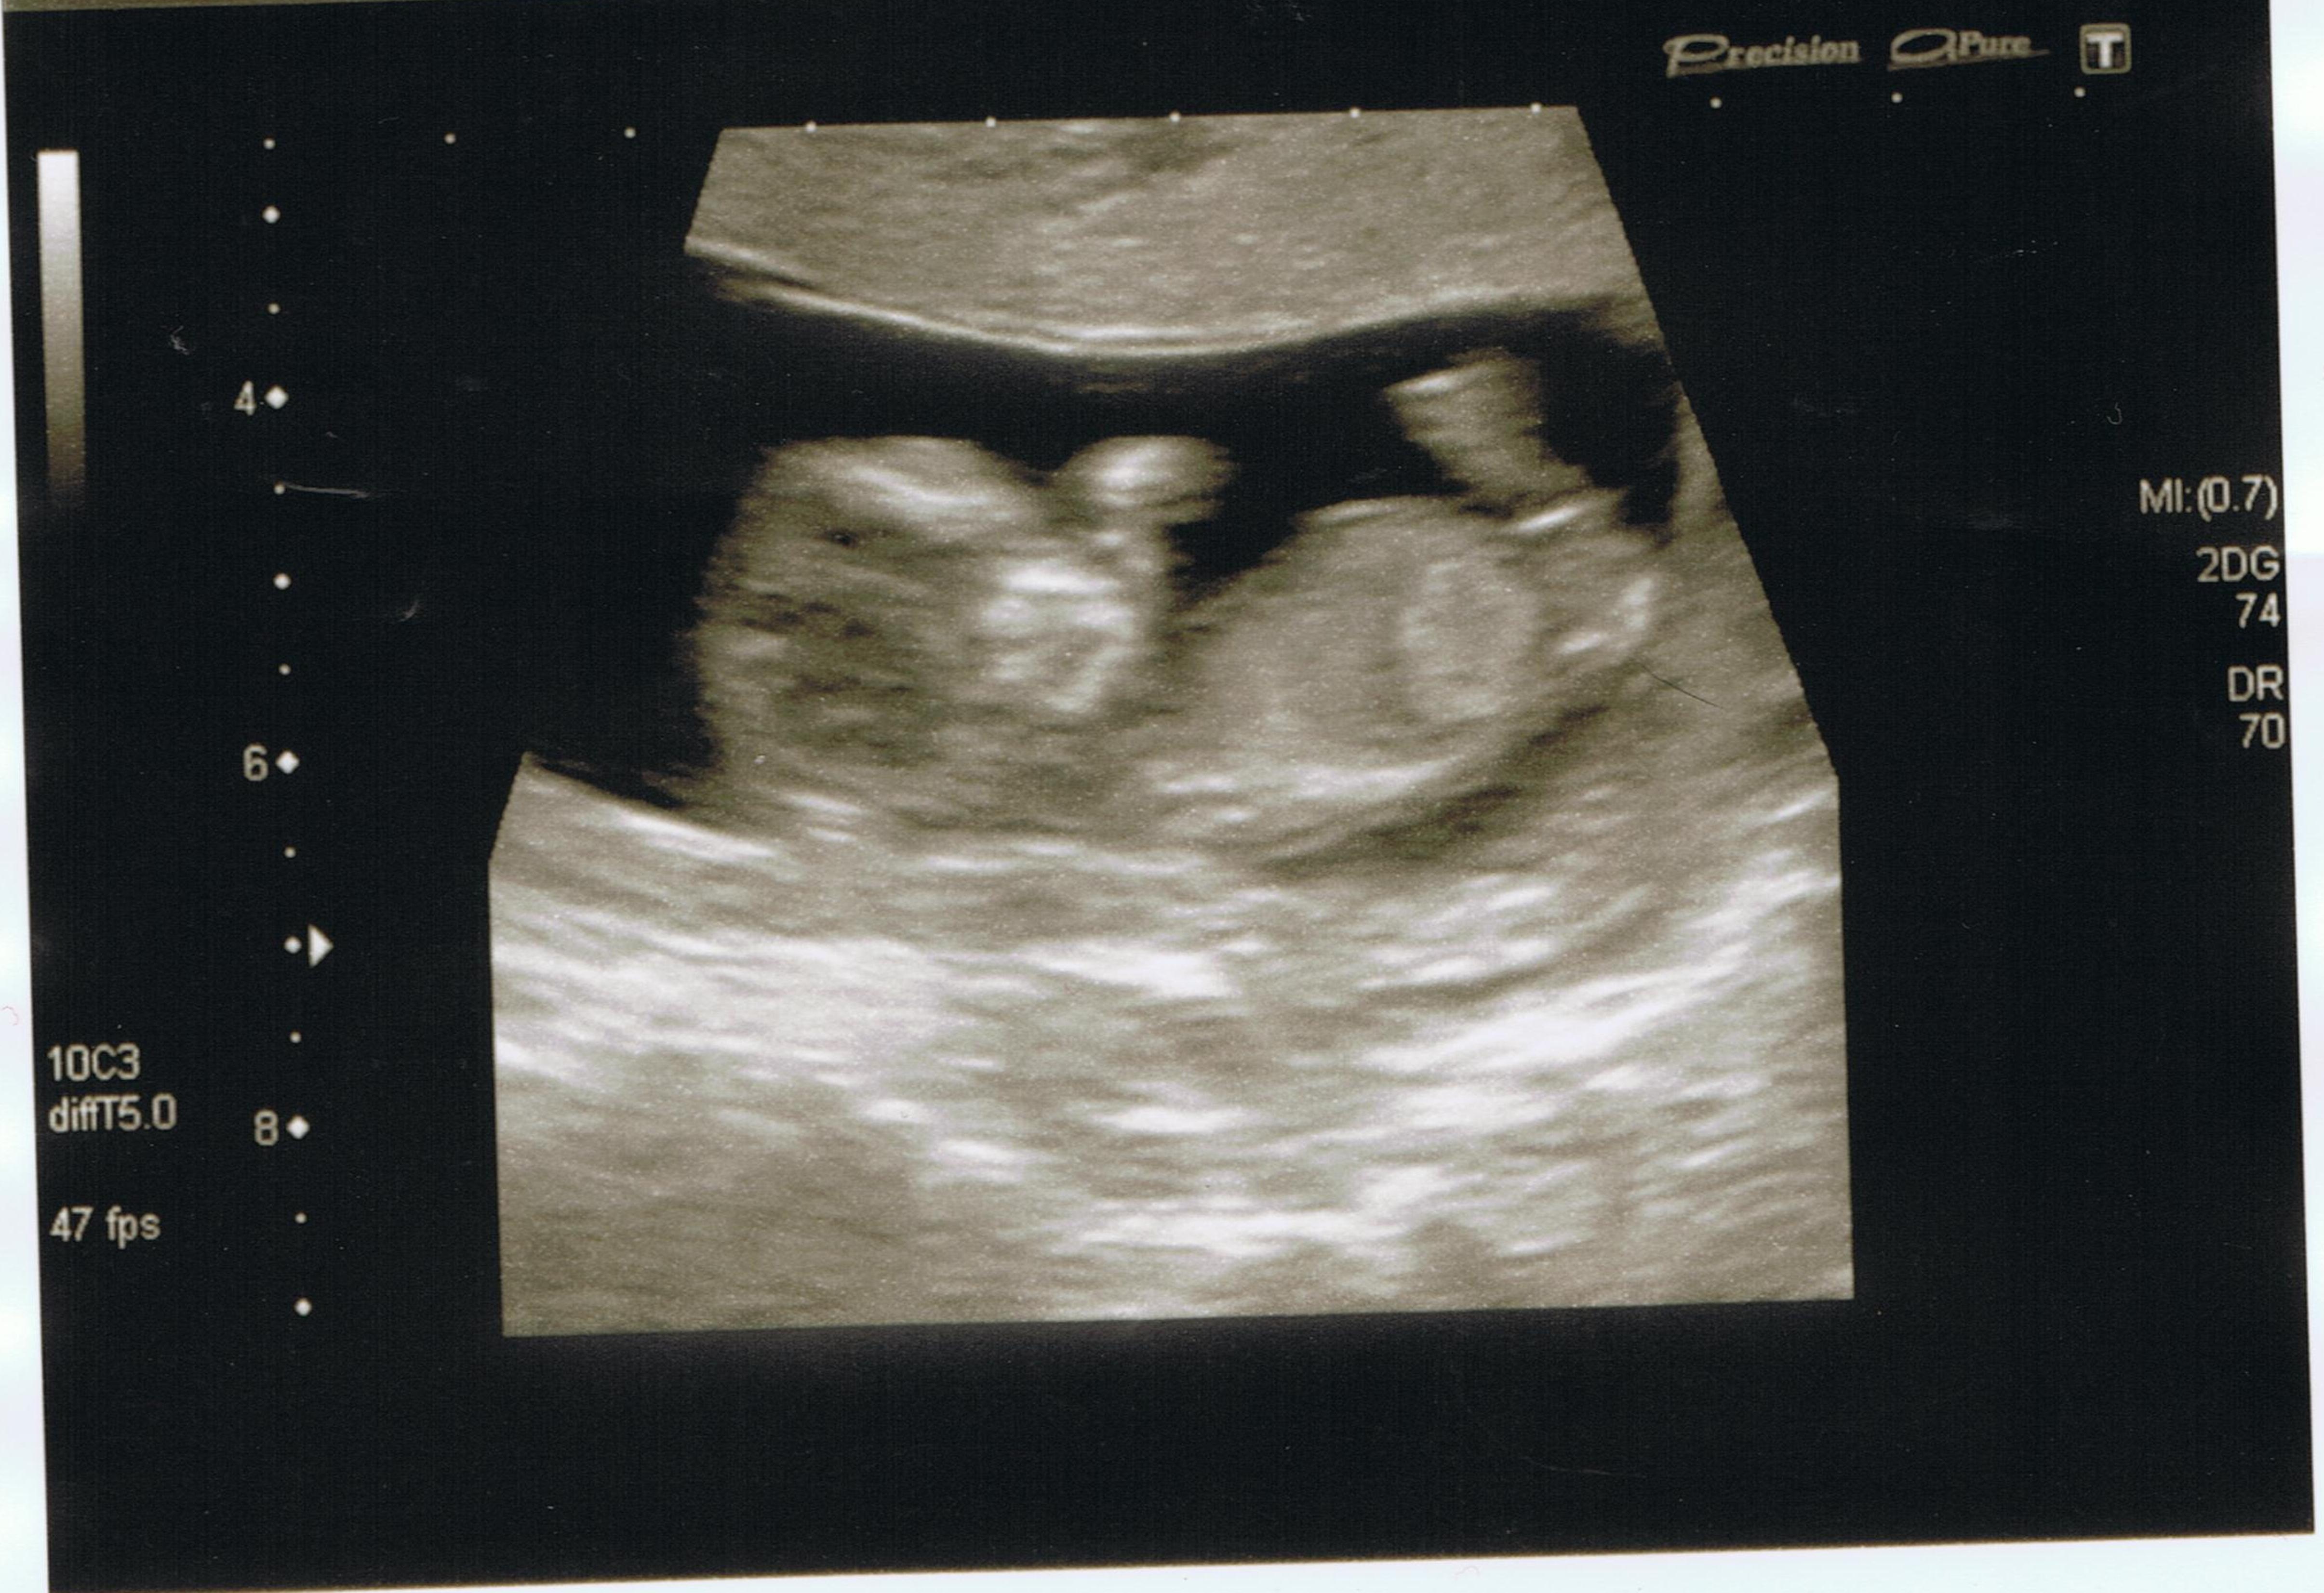

I am sure i am having another little man to add to my collection, but before i met you lovely ladies i had not even heard of the nub shot theory. i had my dating scan yesterday and am 12 weeks here is a copy of my shot in the hope that you can shed the light of your wisdom and give me some idea of what you think. thank you.